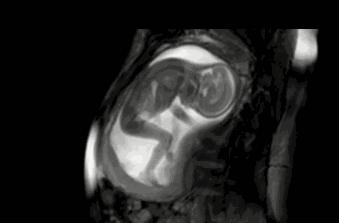

孕妈咪的感觉:宝宝在腹内拳打脚踢,在这个阶段,宝宝正处在活跃期,而且子宫内环境也相对宽敞,所以胎宝宝的活动空间充足, 此时的胎动也是最激烈的。孕妈咪可以经常感觉到宝宝的胎动,因为宝宝此时正在妈咪腹内拳打脚踢、翻滚呢。如果注意,还可以再肚皮上看到凸起的小手和小脚。从这时候开始,一直到接下来的十几个星期,都将是胎动活跃的时期。

孕妈妈的感觉:宝宝在腹内拳打脚踢,在这个阶段里,宝宝可能开始打嗝了,所以孕妈咪偶尔会感到肚子阵发性的一跳一跳。此时,孕妈咪的羊膜囊里容纳了多达740毫升的羊水,宝宝可以在里面自由地活动。尽管宝宝能够听到声音已经有一段时间了,但事实上从这时候开始,宝宝才会对外界声音做出反应。孕妈咪可能会发现,当外界突然发出什么声响时,宝宝会在子宫里跳一下来做出回应。

孕妈妈的感觉:宝宝的小胳膊、小腿在捅肚子,在孕期36周时,孕妈咪能够感觉到非常明显的胎动。这时候,宝宝可能已经头朝下蜷曲着身体,摆 好了最终出生时的姿势。如果是第一胎,那么子宫和腹部的肌肉会比较紧,它们能够帮助宝宝保持 这种姿势。此时,孕妈咪能够感觉到宝宝的小胳膊、小腿在捅自己的肚子。有时候,淘气的小家伙 还会把妈妈的肋骨踢得生疼呢。